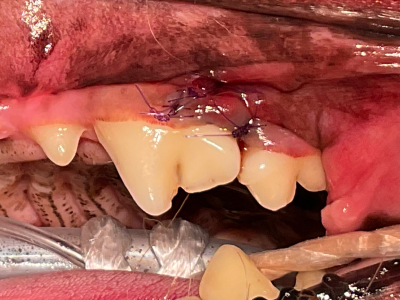

オープンフラップデブライドメント完了

マイクロスコープを用いて根っこの表面を徹底的に清掃します。

縫合完了

歯肉を縫合して元に戻し治療終了。